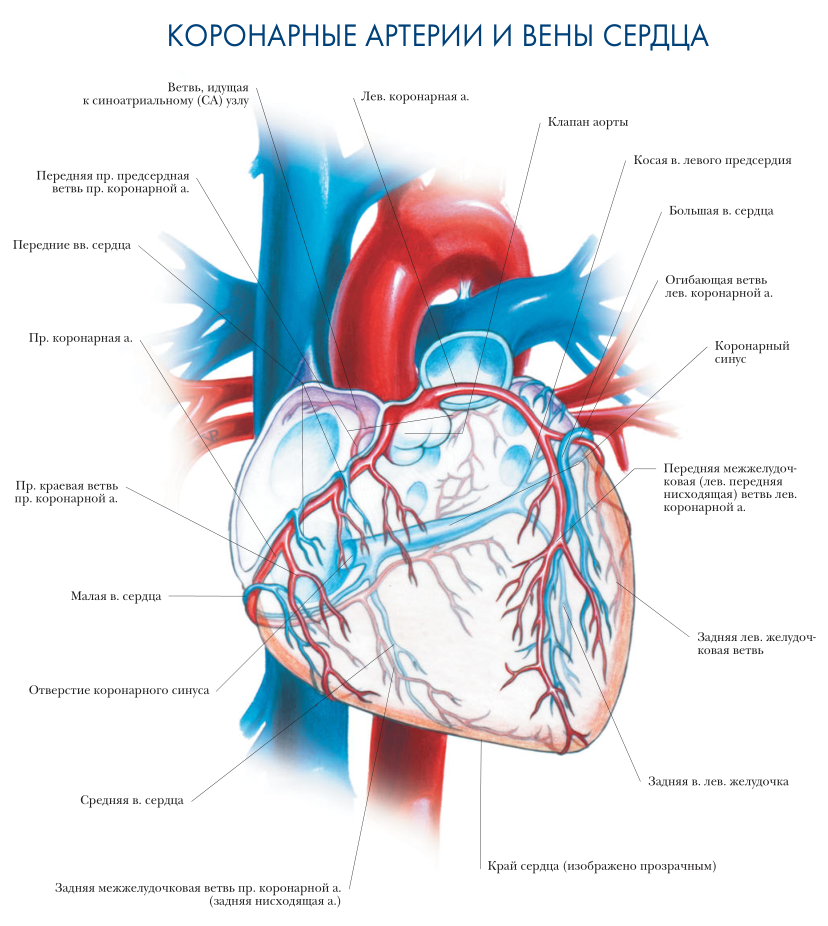

Особенности и диагностика левостороннего кровотока